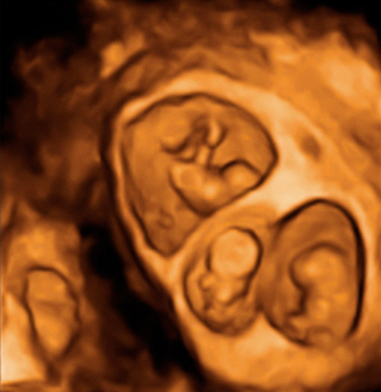

Ecografía 3D de la semana 9: Trillizos

Cada uno de los bebés crece en su bolsa amniótica

En esta ecografía en tres dimensiones (3D) se ve un embarazo de trillizos de 9 semanas. Uno de los bebés, "crece" solo dentro con una bolsa y placenta independiente. Más abajo se aprecian a otros dos bebés que también se desarrollan en bolsas independientes.

Ecografía de trillizos de 9 semanas en 3D

En la imagen se ve un embarazo de trillizos de 9 semanas tomado por un ecógrafo en tres dimensiones (3D). Se diferencia perfectamente en la parte superior de un primer bebé "en solitario" con su bolsa y placenta independientes. Una membrana gruesa le separa de sus hermanos, que se gestan con él en el útero materno. Precisamente en la parte inferior de la imagen podemos observar a los dos gemelos en bolsas también independientes, con una fina membrana de separación entre ellos.